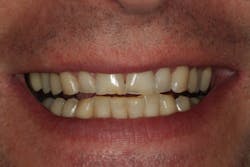

Through working with Darren, we were able to provide the necessary treatment to obtain the five requirements of occlusal stability. He now has stable stops on all teeth, anterior guidance in harmony with the envelope of function, anterior teeth that provide immediate posterior disclusion in protrusive, and he no longer has working and balancing side excursive interferences.

Overall, the case closely followed our treatment plan blueprint because of proper diagnosis and planning. Darren was comfortable with his envelope of function, occlusal stability was restored, and he was thrilled with his natural, esthetically pleasing smile.